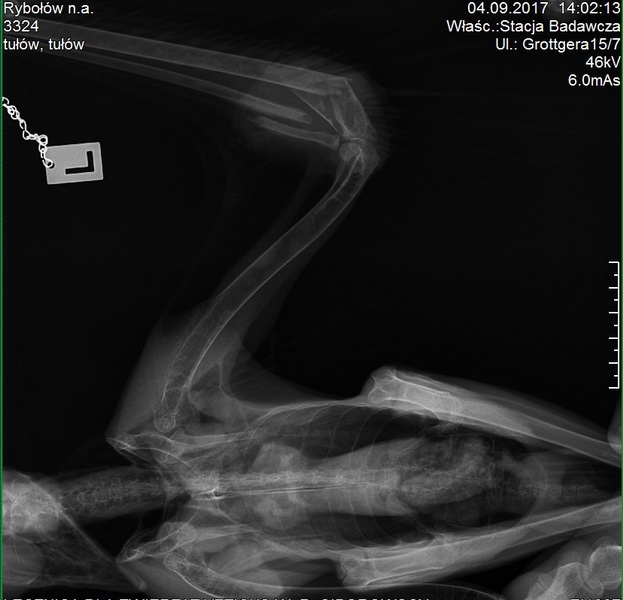

Specjalnością ośrodka pozostaje leczenie i rehabilitacja ptaków drapieżnych, jednak przyjmowane są tu również inne zwierzęta gatunków chronionych. W latach dawniejszych trafiały tu ptaki drapieżne z różnych, czasem odległych regionów kraju. Większość z nich udaje się przywrócić naturze jednak niektóre, z trwałymi urazami, muszą pozostać tutaj lub w innych placówkach do końca życia. Niestety, czasem zdarzają się też upadki czy eutanazje.

W Stacji znajdują się np. orły przednie czy bieliki utrzymywane przez 20 – 40 lat! Główną przyczyną niesprawności dzikich zwierząt są kontuzje i urazy, okresowe osłabienia młodych osobników, rzadziej choroby czy zatrucia. Najczęściej trafiają tu zwierzęta gatunków pospolitszych jak myszołowy, pustułki, bociany czy jeże. Zdarzają się jednak i bardzo rzadkie, jak orły przednie, rybołowy czy nawet sępy. Wszystkie dostarczane tu zwierzęta znajdują fachową pomoc oraz opiekę, do czego czujemy się zobowiązani i robimy od wielu lat bez modnego obecnie rozgłosu medialnego.